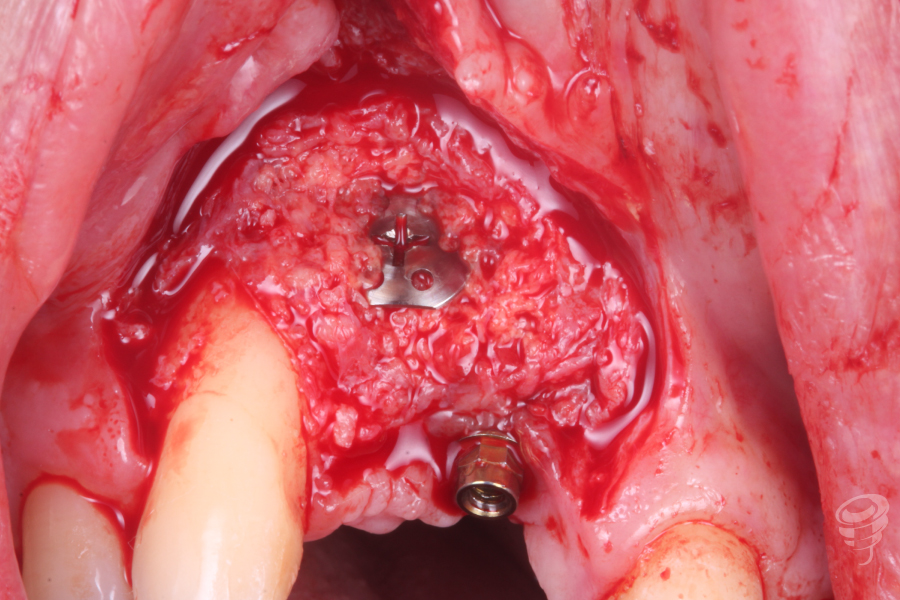

Colocamos un tornillo de Tent Pole en la zona del defecto creado por el implante en 12 para conseguir un relleno óseo adecuado.

Imagen 5

Imagen 6

Una vez estabilizado el tornillo Tent Pole, manteniendo la distancia al hueso remanente, procedemos a rellenar con hueso autólogo de fresado y xenoinjerto. Posteriormente colocamos una membrana de colágeno fijada con chinchetas. (Imagen 7 y 8). Finalmente procedemos a realizar la sutura.